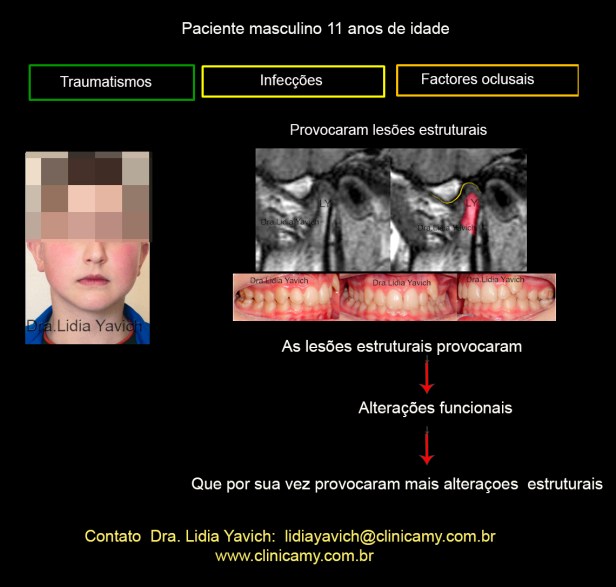

Paciente de sexo masculino com onze anos de idade se apresenta na consulta com queixas de dor de cabeça, dor na nuca, dor nos ombros, dor no pescoço, adormecimento e formigamento nas mãos e DIMINUIÇÃO DA ABERTURA BUCAL.

Na história clínica do paciente em questão é relevante na análise do caso o antecedente de traumatismos no mento na primeira infância assim como as infecções repetitivas de ouvido e garganta e uma pneumonia que o paciente teve com oito meses e que precisou de internação hospitalar.

Lesões estruturais podem produzir alterações funcionais que por sua vez aumentam as alterações estruturais.

Alterações estruturais e funcionais.

Mesmo uma articulação descomprimida demora em recuperar-se.

Algumas lesões estruturais podem ser recuperadas OUTRAS NÃO.

Mesmo uma articulação descomprimida demora em recuperar-se.

Algumas lesões estruturais podem ser recuperadas OUTRAS NÃO.